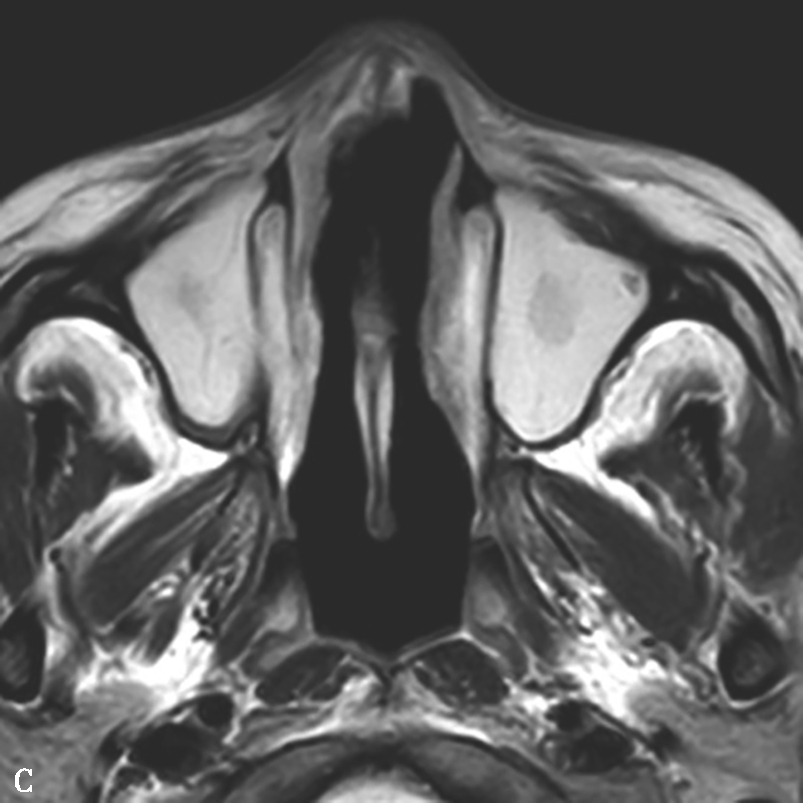

图1-3-20 慢性鼻窦炎

A~C.横断面、冠状面及矢状面CT平扫,示右侧额窦、上颌窦黏膜增厚,窦腔内可见软组织密度影,窦口鼻道复合体狭窄,右侧上颌窦窦壁骨质增生硬化、肥厚;D~F.同一患者横断面MR T 2 WI、T 1 WI及横断面增强T 1 WI,示右侧上颌窦黏膜增厚,呈T 1 WI等信号、T 2 WI高信号影,增强扫描示右侧上颌窦黏膜线样强化